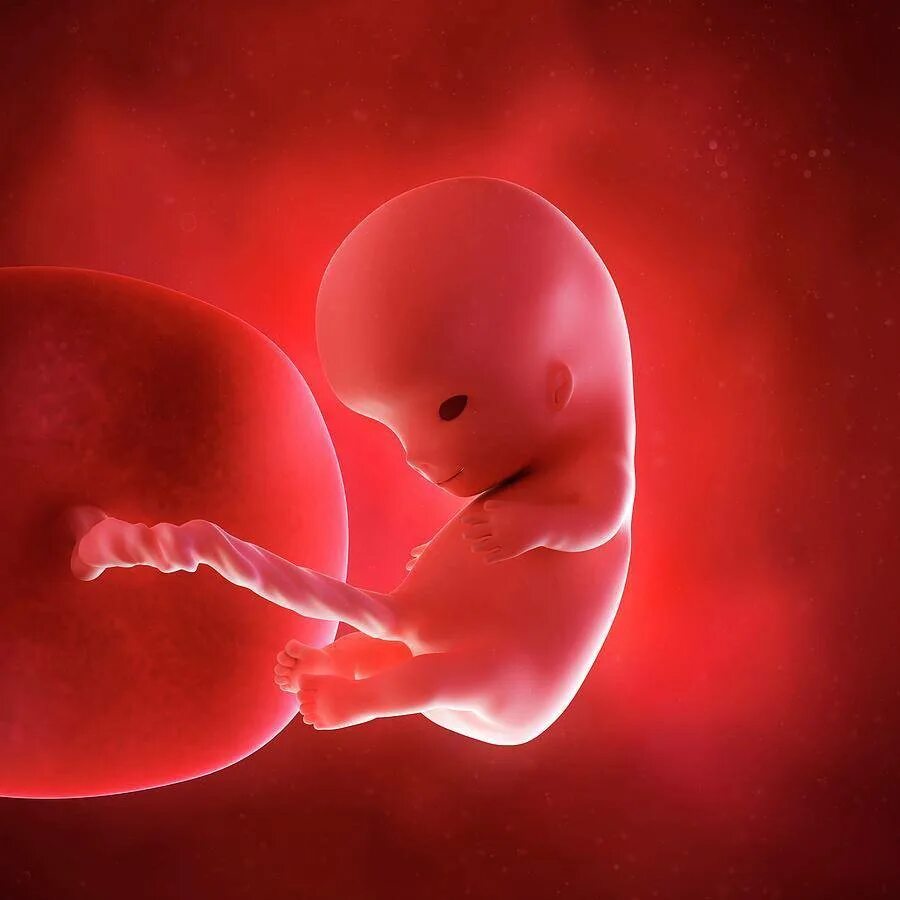

Плод 10 см